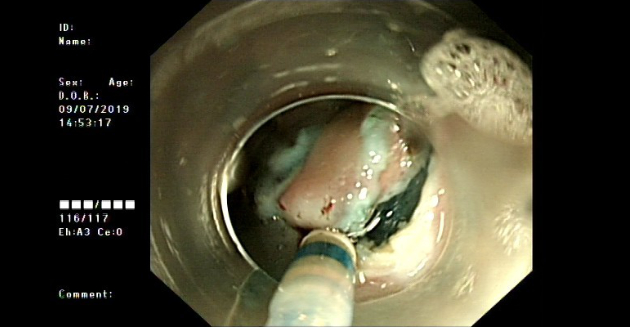

In 2019, ultrasound endoscopy still indicated a submucosal bulging mass on the lesser curvature of the gastric antrum, and submucosal ectopic pancreas was considered. (Figure 2).

ectopic-pancreas-fig2-pc

Figure 2. Ultrasound endoscopy indicated a submucosal bulging mass on the lesser curvature of the gastric antrum (red arrow)